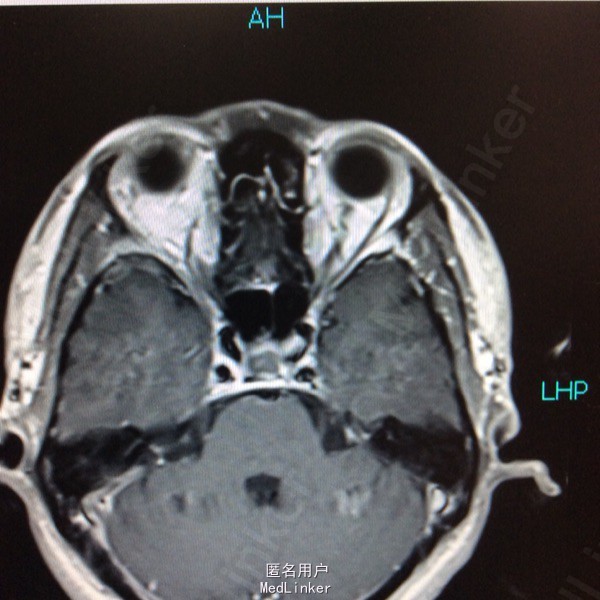

男性,31岁,头痛起病,无恶心呕吐,无视力改变。

查体未见明显阳性体征,发育正常 头颅CT提示鞍区少量出血 MRI增强提示鞍区占位病变,大小约0.8*1.5cm 考虑垂体瘤卒中

术前诊断:垂体瘤 择期行经蝶入路垂体瘤切除术 术后病理提示垂体腺瘤